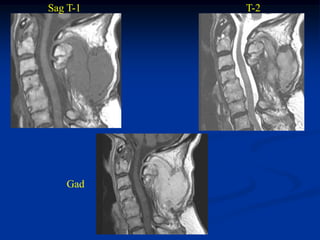

Case #1170.2         Axial T-1          T-2   P.O. desmoid

82 yr female who noted a

slow growing tender mass

at the site of a prior cervical

laminectomy

Gad

Sag T-1   T-2